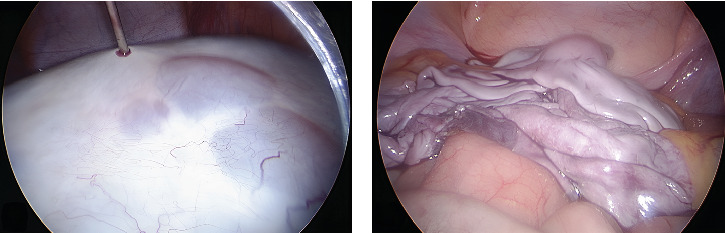

Objective: To present a rare diagnosis of polycystic ovary syndrome (PCOS) after initial suspicion of malignancy. PCOS is a common endocrine disorder in adolescence characterized by hyperandrogenism and polycystic ovaries. Case Presentation: A 13-year-old female patient was referred for a giant mass noted on examination for metrorrhagia. She had previously presented for hirsutism and acne, treated independently. A multicystic abdominal tumor measuring 21 × 17 × 9 cm was identified, with a nodular image and negative tumor markers, but elevated testosterone and LH/FSH ratio. Therefore, video-assisted ovarian cystectomy was performed. Finally, the patient was diagnosed with PCOS and began hormonal therapy, with improvement of hyperandrogenism. Conclusion: In adolescents with large ovarian cysts, in addition to ruling out malignant neoplasms, PCOS should be considered as these may have similar clinical and radiological presentations.